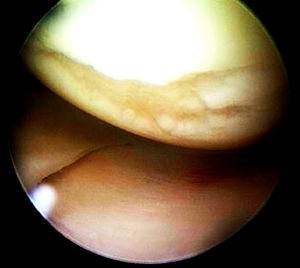

2. Innenmeniskus-Riss

Meniskus (M) ist eingerissen, sodass sich ein Lappen (m) gebildet hat. Davor ist ein freies Knorpelstückchen zu sehen.

Mit entsprechender Erfahrung ist es möglich, einen eingerissenen Meniskus arthroskopisch, also über die kleinen Hautschnitte zu operieren – ein enormer Fortschritt gegenüber der früher üblichen Eröffnung des Kniegelenks [Arthrotomie].